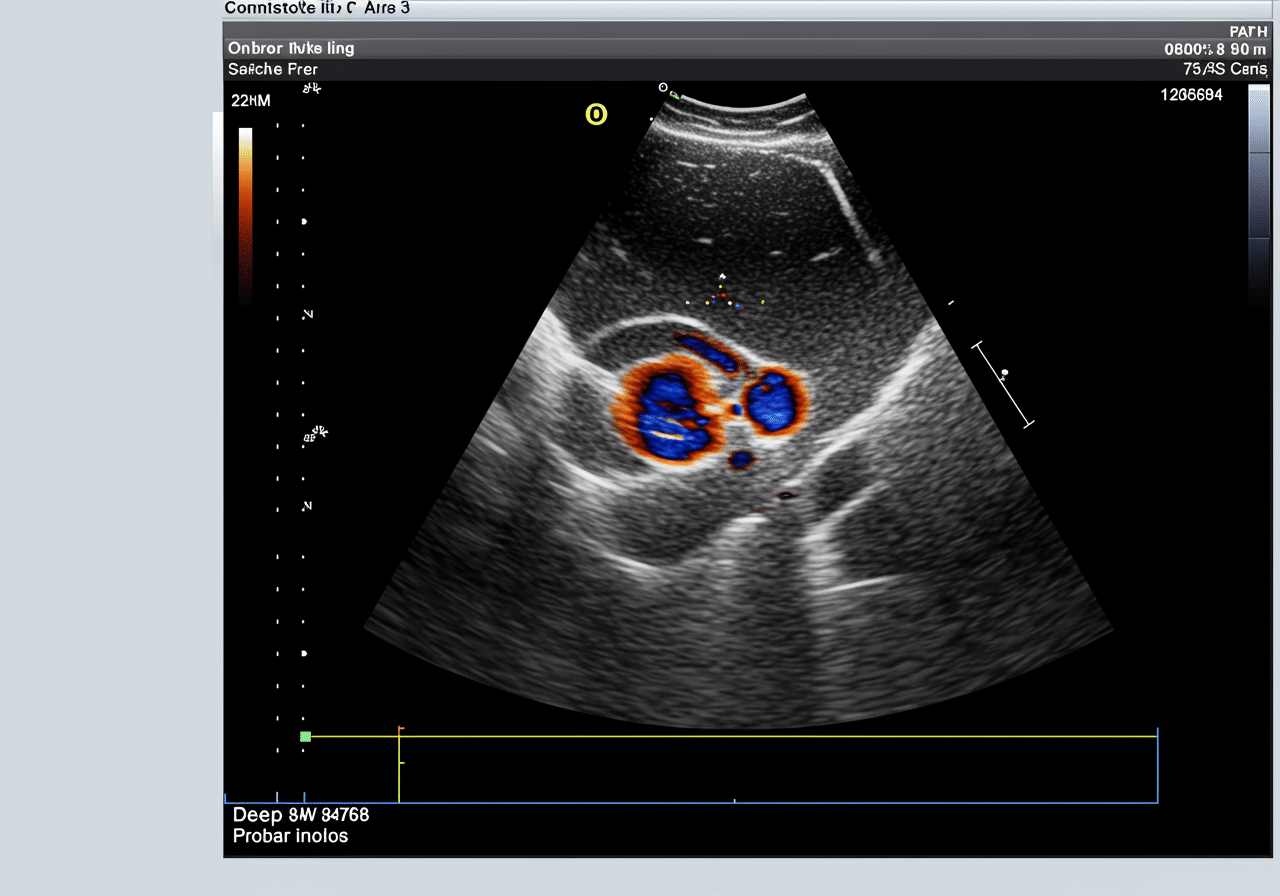

Advanced Vascular Doppler Technology: Beyond Basic Urgent Care

Priority ER's diagnostic capabilities for vascular doppler ultrasound for deep-vein thrombosis exceed Joint Commission standards for emergency departments[14], featuring equipment typically found only in specialized vascular centers. Our duplex doppler system produces images with 30% better resolution than standard urgent care facilities, enabling detection of small thrombi, valve incompetence, and venous obstruction as subtle as 1mm[15]. The integration of PACS (Picture Archiving and Communication System) technology allows instant image transmission to consulting vascular surgeons when complex DVT requires specialized anticoagulation planning.

Can Priority ER perform vascular doppler for pulmonary embolism screening?

Absolutely. Our duplex doppler system provides immediate lower extremity venous imaging for DVT source identification, while our CT scanner performs pulmonary angiography for PE diagnosis. Board-certified emergency physicians interpret both vascular doppler and CT imaging within minutes, enabling rapid treatment decisions for thromboembolism, chest pain, or respiratory cases. We also offer comprehensive pulmonary emergency care with advanced diagnostics beyond basic doppler imaging.

Our vascular-trained staff ensures comfortable doppler experiences with minimal anxiety. The process takes 15-25 minutes and is completely painless - you simply lie still while the sonographer applies gel and moves the transducer along your leg to visualize blood flow. Our vascular emergency specialists use advanced color-flow imaging and compression techniques, with immediate physician interpretation following ACEP guidelines.